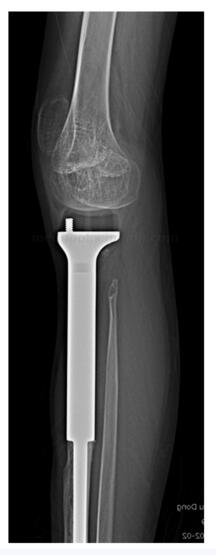

图47‐8 术后5年X 线左胫骨上段

图47‐9 术后5年X 线左胫骨上段侧位

:患者术后未见明显并发症。目前患者术后5年,未发现局部复发及远隔转移。患者跛行步态。左膝关节主动活动度(伸直至屈曲):0~90°。下肢长度测量显示左胫骨较右胫骨短缩4.4cm,左股骨较右股骨短缩约3.1cm(图47‐7)。X 线显示假体未见明显松动,膝关节无脱位(图47‐8~图47‐10)。患者站立时由骨盆及脊柱倾斜来调整肢体长度(图47‐11)。

图47‐10 术后5年X 线显示假体未见明显松动,膝关节位置无脱位a﹒正位片;b﹒侧位片